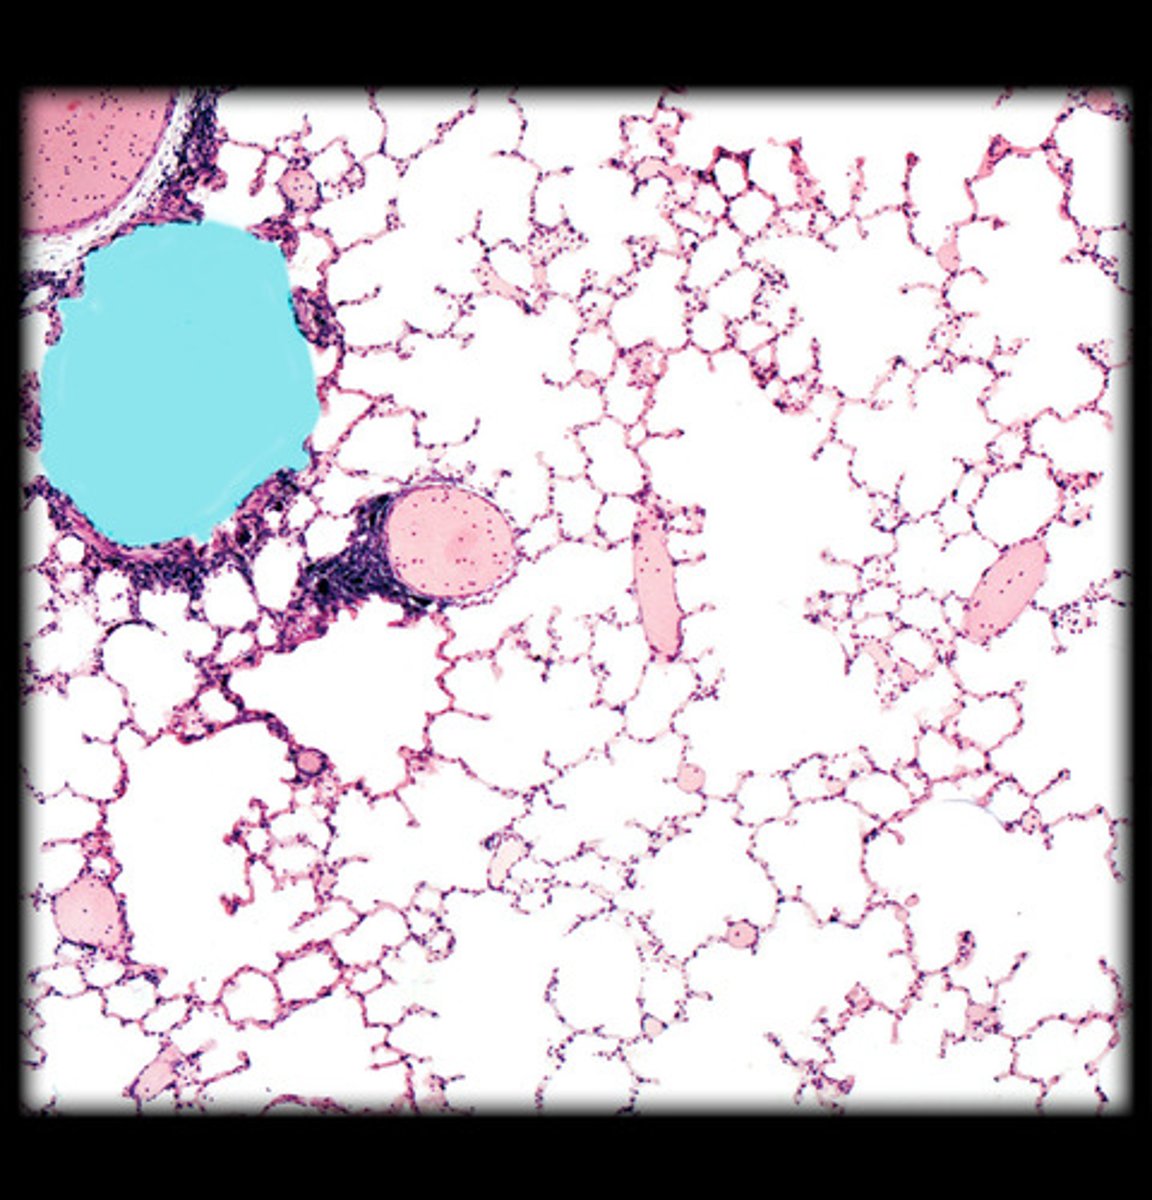

alveolar duct - whole

what is highlighted HM in this image?

alveolar duct